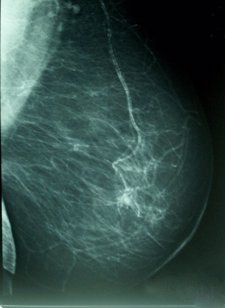

Cáncer De Mama, Densidad MamográficaInvestigadores del Centro para el Cáncer Memorial Sloan-Kettering, en Nueva York (EEUU), han demostrado que un nuevo virus-vacuna, actuando como un agente oncolítico y anti-angiogénico, puede eliminar las células del cáncer de mama triple-negativo (CMTN). Los resultados del estudio, presentados en el último Congreso Clínico Anual del Colegio Americano de Cirujanos, podrían conducir a una terapia más específica contra esta forma mortal de cáncer de mama.